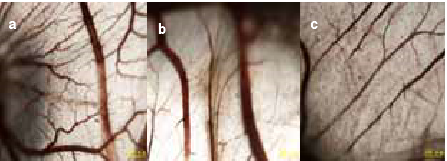

肿瘤血管生成是肿瘤供养和转移的重要基础,如果能有效抑制肿瘤血管生成,将在很大程度上抑制肿瘤的生长和转移。在鸡胚绒毛尿囊膜模型试验中,做了三组试验,一组不加褐藻寡糖,其他两组分别加入100ug/ml和200ug/ml褐藻寡糖,发现褐藻寡糖能够显著抑制血管生成,切断肿瘤细胞的营养来源,进而达到阻止癌细胞扩散的目的。正常血管分布由大血管和毛细血管相互联接,小血管发育完全,呈叶脉状分布(图a)在含有褐藻寡糖的两组中,分支血管明显减少,毛细血管稀疏,加褐藻寡糖的两组血管生长率分别降低了60%和80%。

对照组(未加褐藻寡糖)  100ug/ml褐藻寡糖组   200ug/ml褐藻寡糖组